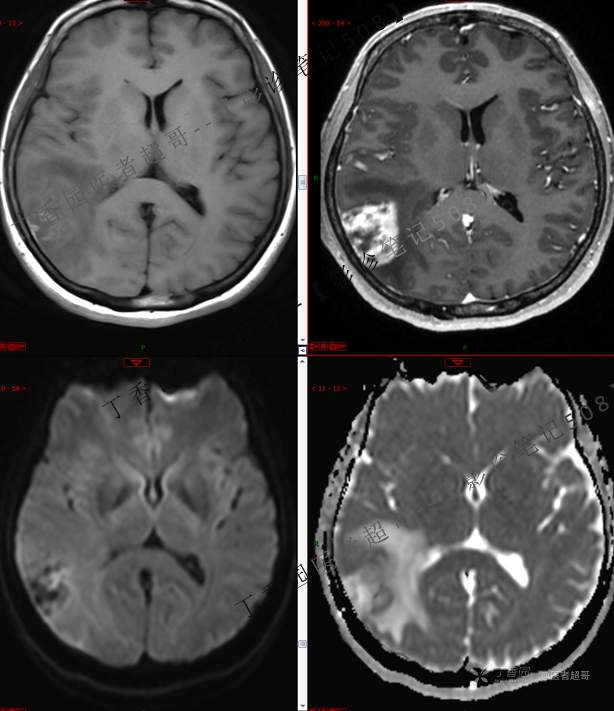

【影诊笔记508】同病异影,个人感觉有难度,欢迎分析,领丁当!有详细术程及病理!

患者性别:女

患者年龄:46岁

主 诉:突发一过性意识不清伴肢体抽搐5天余。

现病史:患者5天余前无明显原因及诱因出现一过性意识不清,伴肢体抽搐,持续约2-3分钟,后意识逐渐恢复,无明显头痛头晕,无恶心呕吐,无肢体抽搐,无呼吸困难,无二便失禁,后就诊于当地医院,行颅脑CT示“颅内占位性病变”,予以药物对症治疗,具体不详,门诊以“颅内占位性病变”,收入我科。患者自发病以来,未进饮食,近期体重无明显变化。